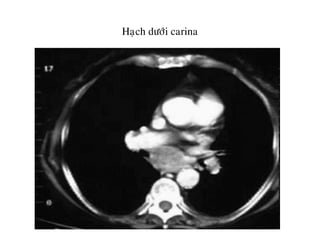

Haïch döôùi carina

• 7. Döôùi carina

7.NHOÙM HAÏCH DÖÔÙI CARINA